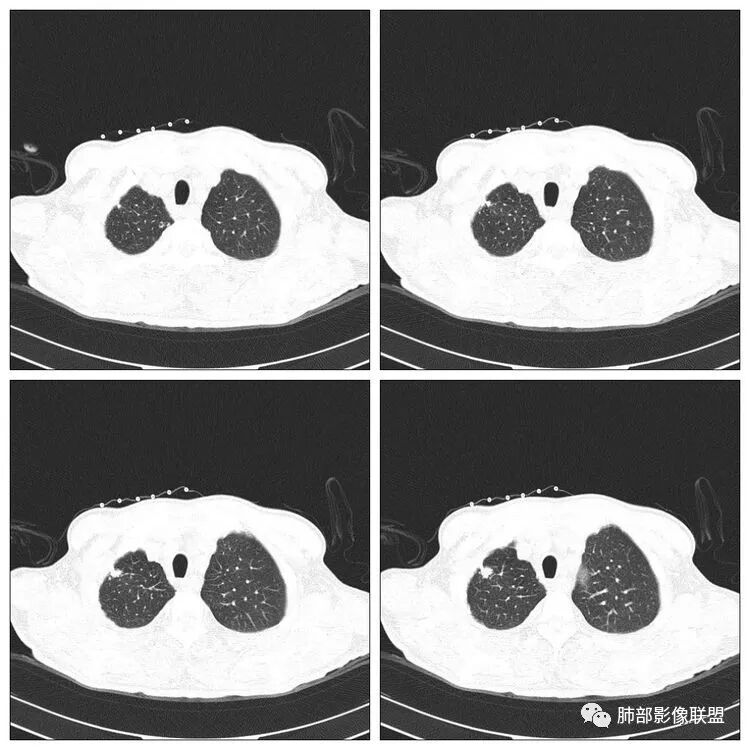

右肺上叶尖段病灶,边缘长、软毛刺,U型征,局部胸膜增厚牵拉,卫星灶。纵隔4R淋巴结增大。

穿越七海的风:右肺上叶病灶,周围卫星灶,U型征,边缘长毛刺,结核首选,恶性肿瘤不能排除。

右侧胸廓稍塌陷,右肺体积稍变小,右肺上叶结节,有膨隆有收缩,局部膨隆明显,见胸膜牵拉,胸膜多发增厚,周围卫星灶,另两肺感觉多发微结节影,应该是有结核的,右肺上叶大结节需警惕合并肺腺癌,建议完善增强和三维重建,另两肺多发微结节,有贲门癌病史,需除外转移瘤。

孙冰伟:老年男性,有贲门癌病史,未提及入院常规检查肺部有问题,右肺上叶尖段病灶,边缘长软毛刺,局部胸膜增厚牵拉,周围有卫星灶。纵隔淋巴结增大,首先考虑良性病变,结核可能性大,建议穿刺活检或CT增强检查。

老年男性,有肿瘤病史,右肺上叶肿块,病灶多发毛刺,胸膜牵拉,边缘考虑月牙铲,病灶见空泡征,病灶体积偏大,有恶性征象我首先考虑肿瘤,鉴别结核。

傅昌瑜:老年男性,有贲门癌史,右上团块影分叶毛刺胸膜凹陷→恶性可能,周围有卫星灶→良性可能。右侧胸廓塌陷,右侧胸膜有较多结节,双侧胸腔少量积液。整体考虑良性可能→结核可能性大。建议增强及穿刺检查。

THINKER:右上肺前段结节,胸膜凹陷征,整体收缩,有空泡征,胸膜多发结节,纵隔淋巴结肿大,双侧胸腔少量积水;考虑恶性,原发腺癌>转移;

前段炎症丶恶性好发,非结核好发部位。

没意见:老年男性,贲门癌病史;CT:右肺上叶前段块状影,病灶由上至下纵轴跨度略长,轴位多个层面提示分叶、膨隆,毛刺,局部平直、内收、凹陷;病灶略散,主体病灶周边卫星灶,支气管树芽征,胸膜增厚,牵拉凹陷,4R淋巴结稍大;整体感觉良恶征象皆有,遗憾没有增强,无法进一步确认,目前转移瘤可能性小,考虑结核可能性较大,需要与原发肺癌鉴别;

老年男性,贲门癌病史。胸CT:右侧胸廓塌陷,右肺体积变小,右肺上叶大结节,深分叶、胸膜牵拉、毛刺,周围卫星灶,两肺多发微结节影,纵隔多发肿大淋巴结,先考虑恶性,结核待排。

小兜:右肺上叶尖段结节,分叶,周边见细长毛刺及胸膜牵拉,周边多发卫星灶,考虑结核可能性大。

丽:右肺上叶尖段近胸膜下结节,部分边缘膨隆,可见胸膜牵拉,周围可见多发播散灶,伴双侧胸腔积液,考虑结核可能大,病人有贲门癌病史,老年男性,恶性肿瘤(转移瘤)不除外。

晨:右尖段病灶,边缘长软毛刺,局部胸膜增厚牵拉,周围卫星灶,纵隔淋巴结增大,首选考虑结核可能。

水晶石头:患者老年男性,术前胸部CT发现。胸部CT:右肺上叶不规则结节影,可见分叶、毛刺、胸膜凹陷、平直征象,周边可疑卫星灶。综合考虑良性病灶,结核可能性大,结合其明确诊断贲门癌,鉴别转移及恶性。

老年男性,右肺上叶实性结节,边缘分叶,周围见较多卫星灶微结节,外侧见胸膜牵拉凹陷征,邻近胸膜反应明显。考虑良性病变,炎性肉芽肿可能,结核可能性较大。鉴于患者贲门癌病史,转移待排,建议穿刺。

阿飞:右肺尖段病灶,边缘长软毛刺,局部胸膜增厚牵拉,周围卫星灶,纵隔淋巴结增大,考虑良性,结核可能。

浪迹天涯:老年男性,贲门癌病史,右肺上叶病灶,局部有深分叶,边缘清楚,周围可见多发点状高密度影,邻近胸膜增厚(其脂肪层可见,未被侵犯),1.结核可能性大,2.腺癌合并结核。

良恶性征象都有,部分层面像多个结节堆积,周围见多发点状,小斑片。考虑结核。鉴别原发癌。

🎀丽🍀:右上肺病灶,呈分叶状、毛刺征,临近胸膜凹陷征,周围可见卫星灶。支持结核。

王秀仙:右肺上叶肿块,边缘有平直收缩,部分边缘膨隆,有分叶,有毛刺,周围见较多卫星灶结节,邻近胸膜反应增厚牵拉;考虑结核。